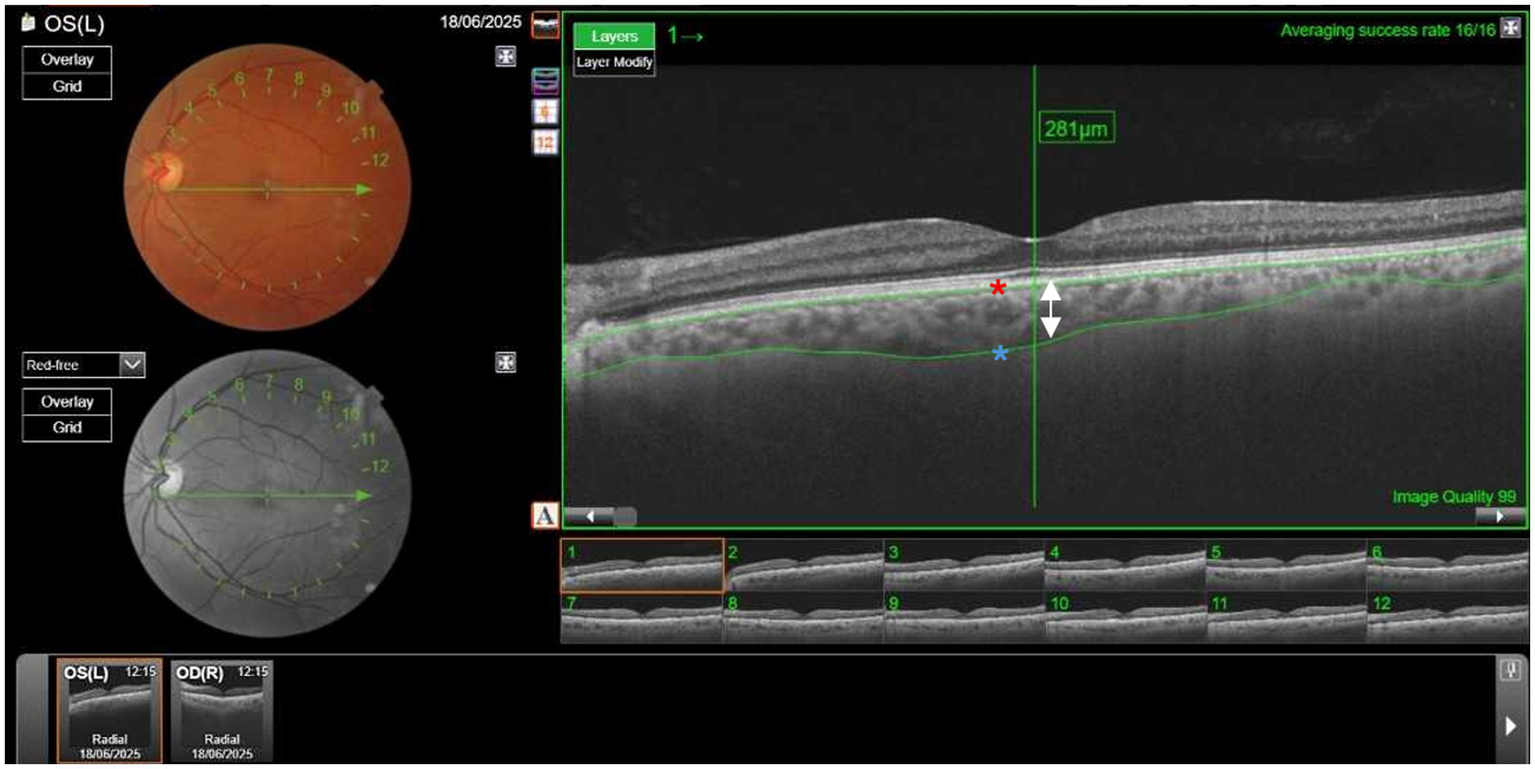

CT was measured using swept-source OCT (Topcon DRI-OCT Triton) (Figure 1). OCT is a non-invasive diagnostic technique that does not use ionizing radiation, is easy to perform, and does not require the use of mydriatic drugs. Swept-source OCT uses light waves with longer wavelengths, allowing greater penetration. The main advantage is an automatic CT measurement. Subfoveal CT was defined as the distance from the outer reflective line of the retinal pigment epithelium to the inner limit of the sclera—choroid junction indicated by a hyperfluorescent surface (Figure 2). CT measurements were obtained for both eyes of all participants. Based on the assumption of correlation between the CT in both eyes, the larger CT value for each patient was used for analysis (25, 26). A common statistical issue in precision studies is whether 1 or 2 eyes of patients should be used. The problem arises because of the greater correlation between the 2 eyes of an individual compared with the correlation between 2 individuals. Exceptions can occur in cases of asymmetric eye disease. According to several studies there are two options. The first option is to use only 1 eye of the individual. The second option is to use both eyes but control for the non-independence of measurements (27). Kim MS et al. (28) found no statistically significant differences in CT between the right and left eye in all corresponding areas. However, the nasal peripapillary and peripheral areas had relatively low correlation coefficients, compared to the macular areas. In our study a subfofeal CT, the regions with no anatomic variations between individuals.

Figure 2

Measurement of choroidal thickness (CT) using Topcon DRI-OCT Triton Swept-Source-Optical coherence tomography (SS-OCT). Subfoveal CT was defined as the distance from the outer reflective line of the retinal pigment epithelium (red asterisk) to the inner limit of the sclera (blue asterisk). The arrow shows the thickness of the choroid layer, in this case, 281μm. (Picture provided by Dra. Esteban-Ortega, Ophthalmology service).